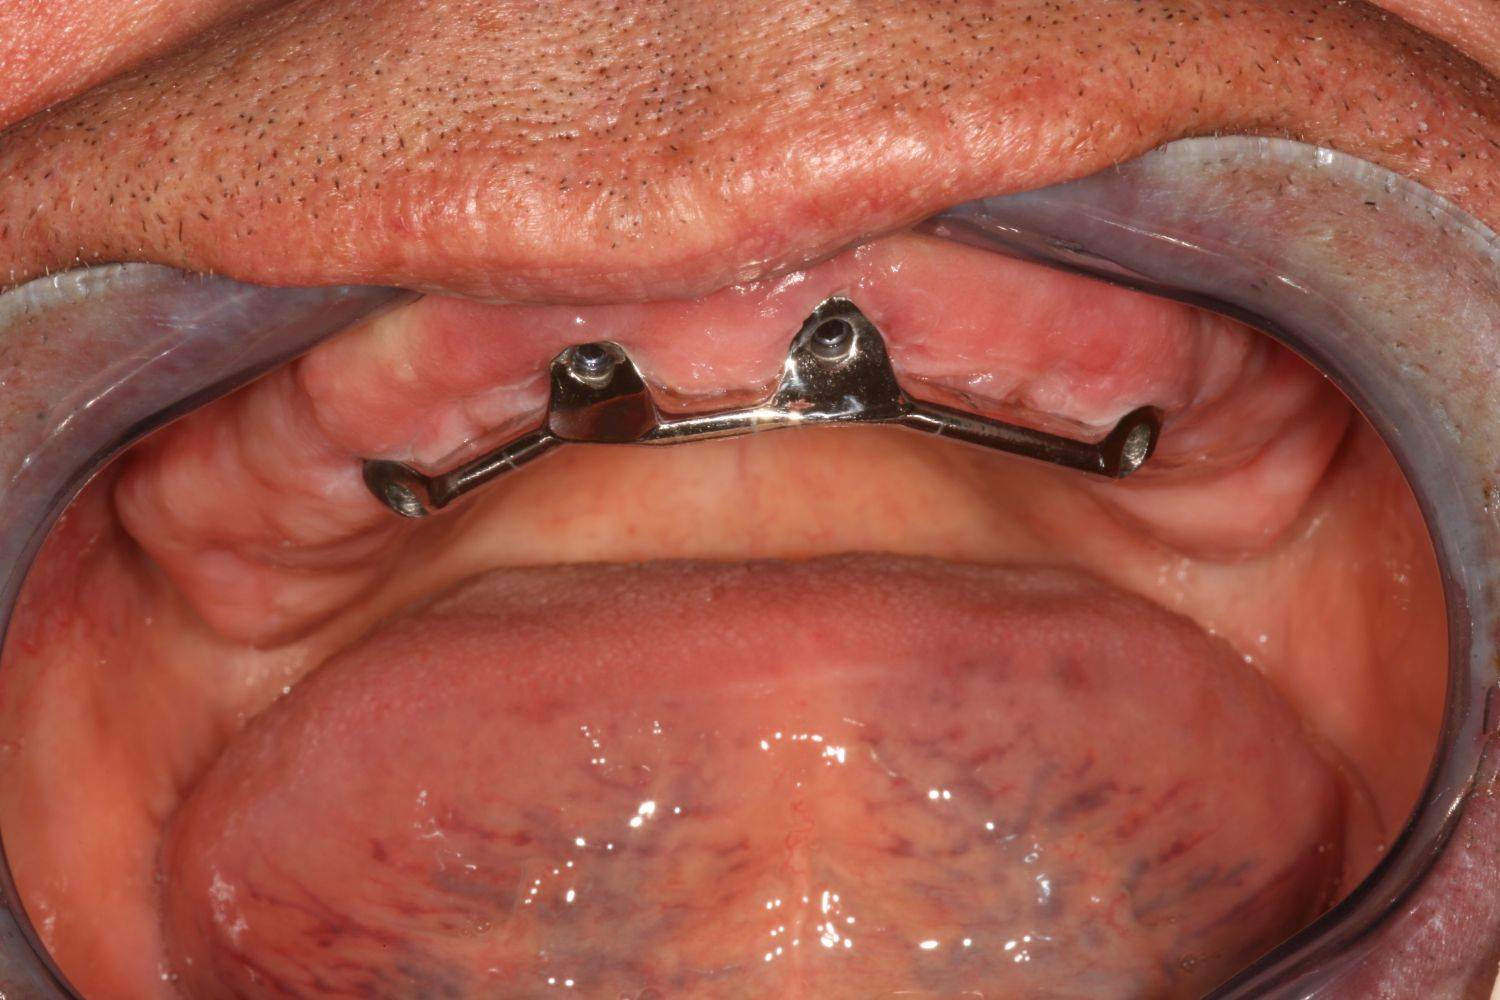

3. eset

4 implantátumra rögzített stéggel stabilizált "Overdenture" megoldás. Költséghatékony módszer fogsorok rögzítésére. Nagyfokú stabilitás érhető el redukált felületeken. Ebben az esetben jól látható, hogy a szájpadlást nem fedi be a kivehető fogsor, az ízlelés is megmarad, mégis javul a rágási képesség és a fogsorok mozgásmentesen rögzülnek.